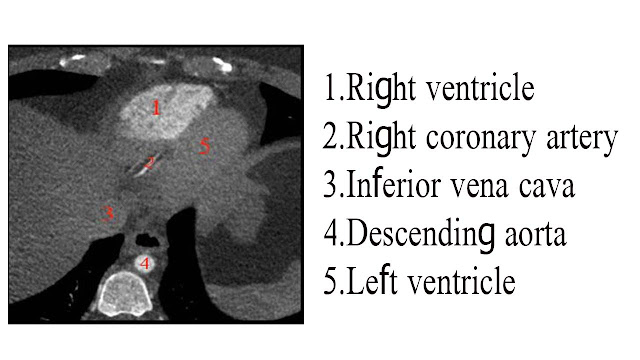

CT scan of heart

_Heart

__axial